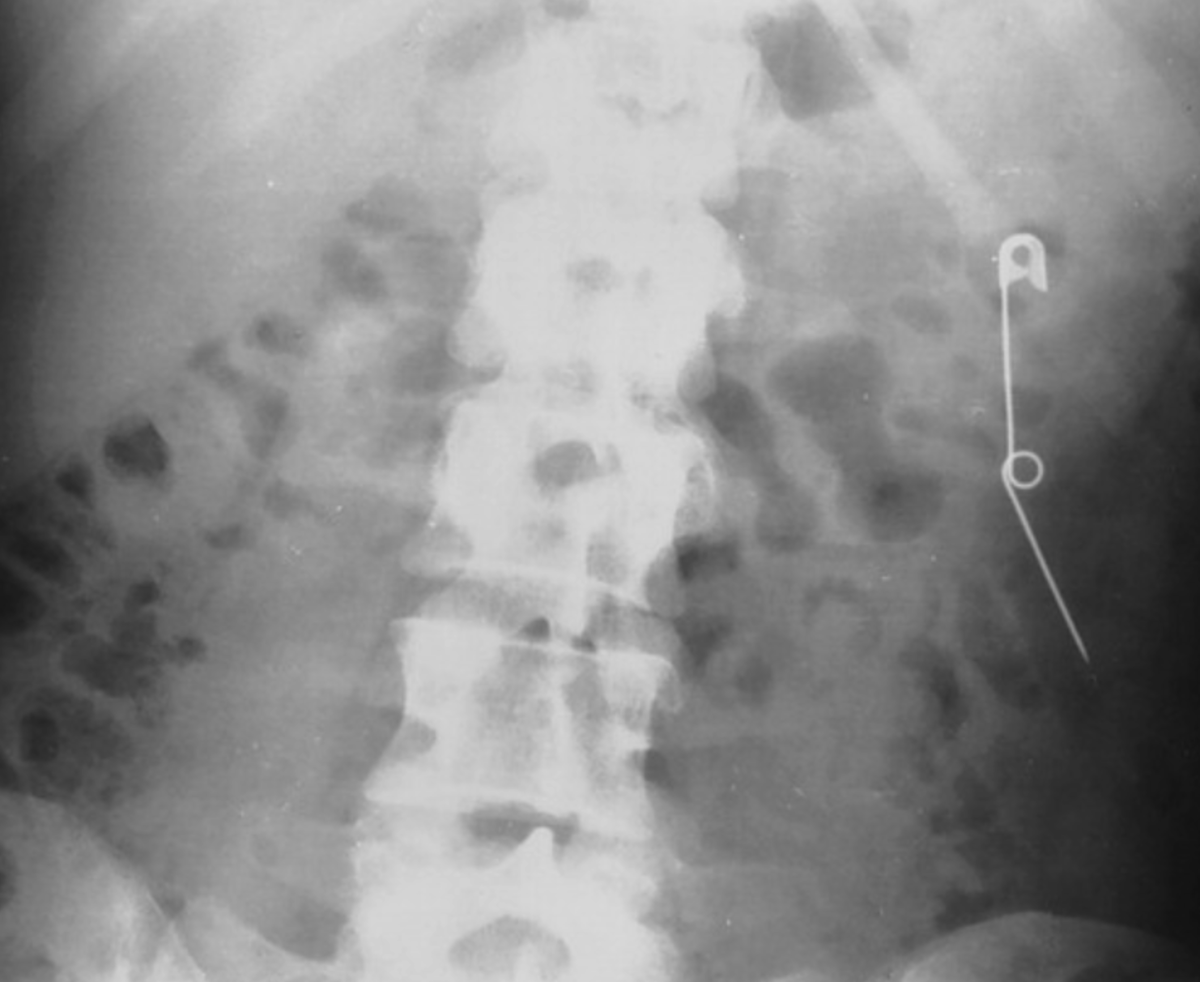

Рентгеновский снимок молодой женщины, которая периодически проглатывала булавки и лезвия бритвы, показывает открытую английскую булавку в нисходящей ободочной кишке.

Рентгеновский снимок молодой женщины, которая периодически проглатывала булавки и лезвия бритвы, показывает открытую английскую булавку в нисходящей ободочной кишке. Что интересно, как сообщили коллеги, булавка вышла без затруднений.